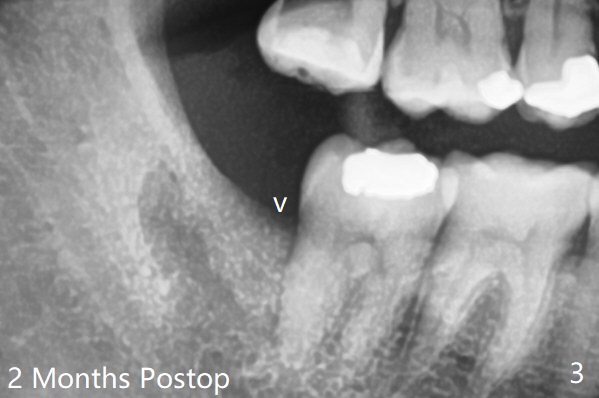

之后在牙槽窝远中,近中放置胶原塞(图二:C)和粘性骨粉(S),上面覆盖PRF,使用4-0 PGA缝线,近中伤口缝合不紧。术后两个月随访时拍摄全景片证实骨粉没有明显流失(病人抱怨术后骨粉流失,逐渐减少),第二磨牙远中没有骨板,第三磨牙近中牙槽嵴接近正常外形(图三:箭头)。